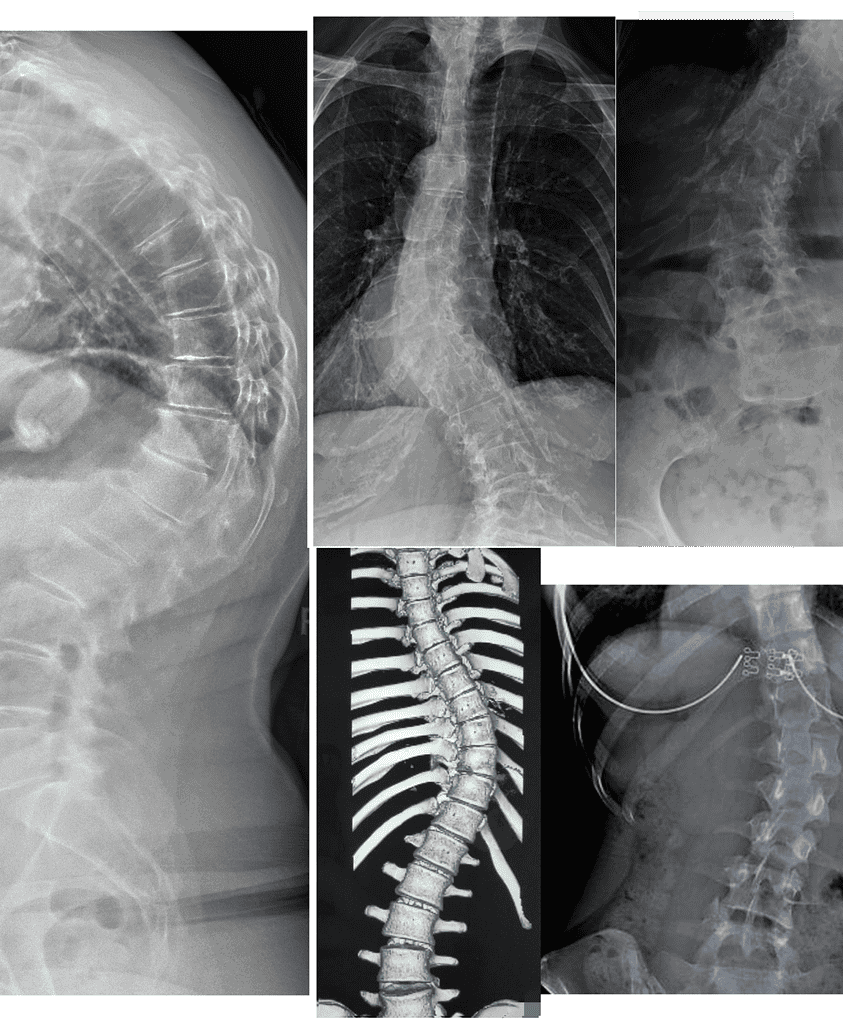

Measurable outcomes on X-ray. Here is what our co-managed patients have experienced.

Note: Individual results vary. All measurements taken on calibrated standing AP radiographs by the treating doctor. Cases shown with patient/guardian consent.

In-Brace Correction is normally 48% but we could see 63%.*

Out-of-Brace curves achieved 37.60% improvement if their curves are 20°-40°.

Results: curve correction: 76.9%, curve stabilization: 23.1%, curve progression 0%